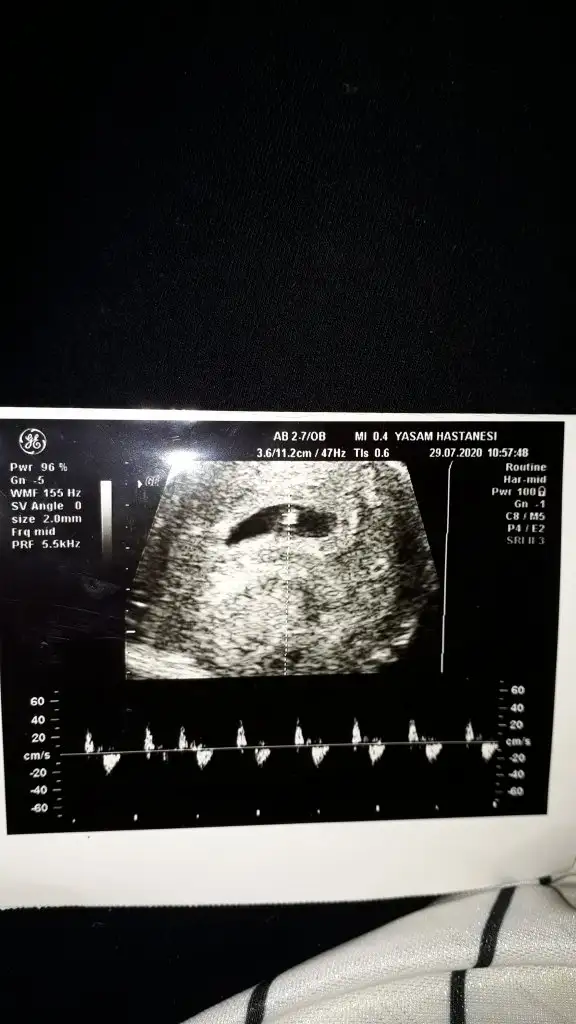

8+3 geç bu teori için yolk saç ne tarafta oluştuysa ona göre yorum yapmak lazım 6 veya 7 haftalık olmalıIkra meyra canım lütfen o güzel tahminlerinden bana da yapar mısın☺ 8+3 günlük karından usg

8+3 geç bu teori için yolk saç ne tarafta oluştuysa ona göre yorum yapmak lazım 6 veya 7 haftalık olmalı